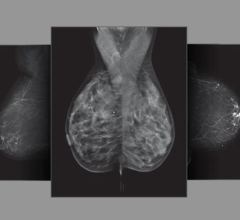

August 6, 2009 - The use of digital breast tomosynthesis and full-field digital mammography (FFDM) combined may be associated with a substantial decrease in recall rate, according to a study performed at UPMC in Pittsburgh, Penn., published in the American Roentgen Ray Society.

An estimated 10 percent of women in the United States are recalled for a second mammogram after an abnormality is detected on the first one. Some researchers believe that digital breast tomosynthesis depicts the breast tissue in a way which may allow radiologists to identify some tumors which could be missed with standard two-dimensional mammography.

In the study, 125 patients were evaluated using a combined method of digital breast tomosynthesis and standard digital mammography. The use of digital breast tomosynthesis and FFDM was associated with a 30 percent reduction in recall rate for cancer-free examinations that would have led to recall if FFDM had been used alone, reported Jules H. Sumkin, M.D., one of the authors of the study.